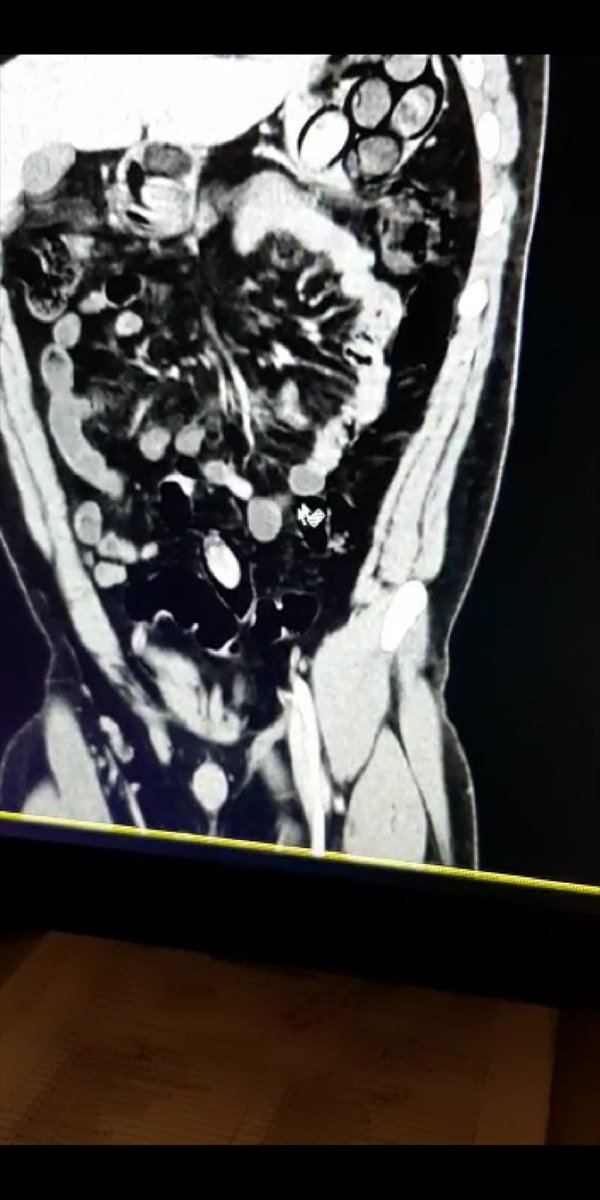

Kontrolde şüphelinin midesinde ve bağırsağında 45 kapsül içerisinde 765 gram eroin olduğu belirlendi.